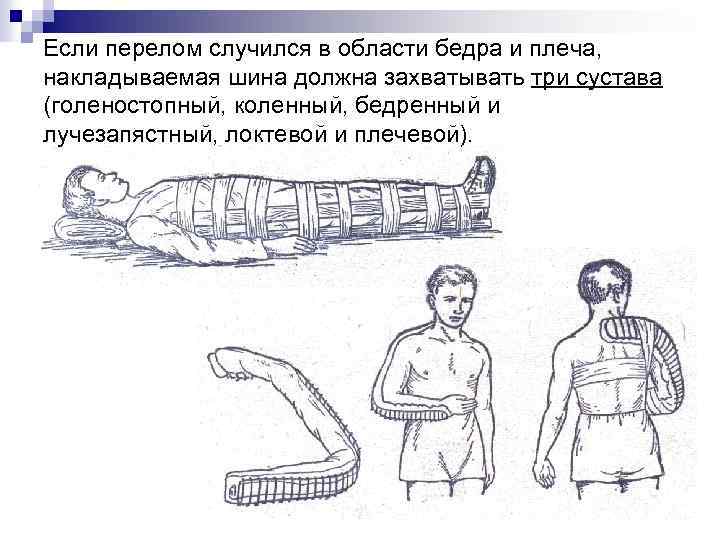

Если перелом случился в области бедра и плеча, накладываемая шина должна захватывать три сустава (голеностопный, коленный, бедренный и лучезапястный, локтевой и плечевой).

Если перелом случился в области бедра и плеча, накладываемая шина должна захватывать три сустава (голеностопный, коленный, бедренный и лучезапястный, локтевой и плечевой).